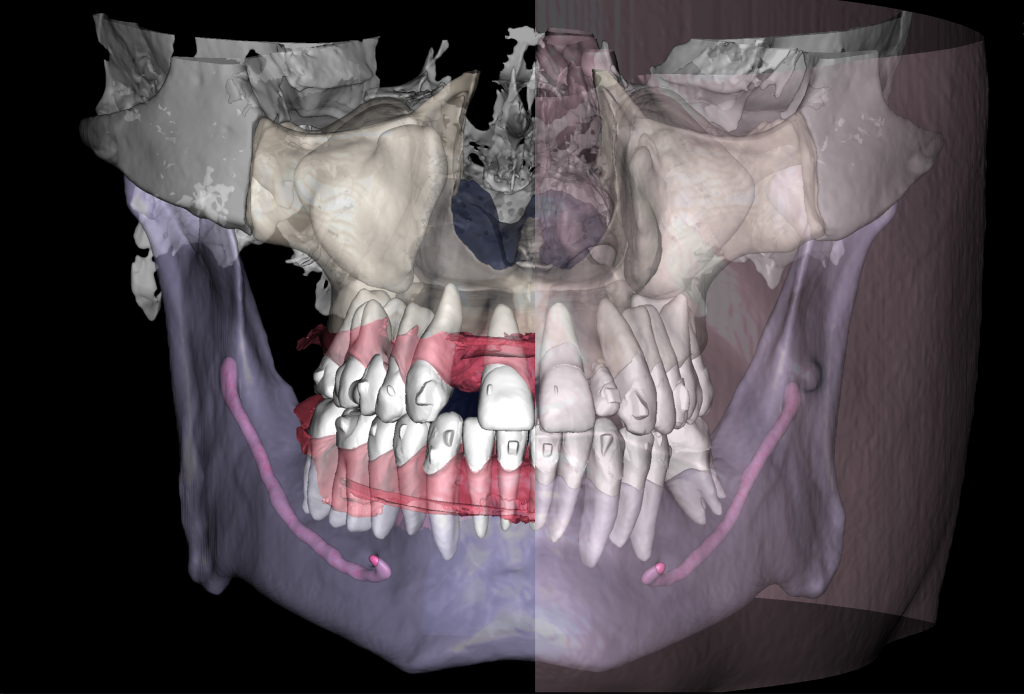

Solution: Diagnocat’s reports, based on CBCT and intraoral scans (STL files), help the clinician to quickly and accurately make decisions about treatment tactics and final tooth position, and to plan comprehensive treatment according to the individual needs of the patient